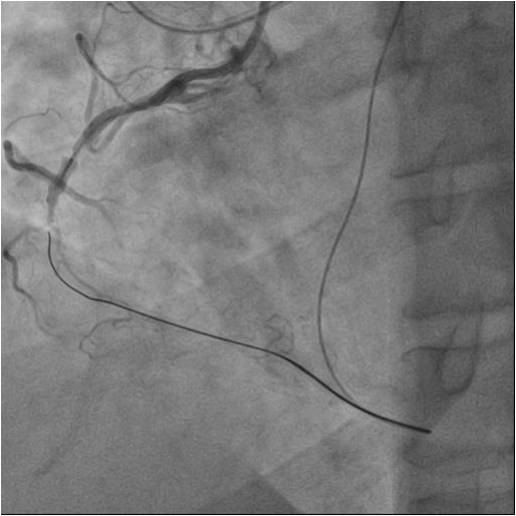

Numerousattempts of antegraderecanalization using guidewires of different stiffnesswere unsuccessful. Pts ofretrograde recanalization using guidewires of different stiffnesswereunsuccessful. Another attempt at antegraderecanalization led to dissection dista RCA. Retrograde recanalization was performed using the technique of «kissing-wire». retrograde guidewire was inserted into theproximal segment of the RCA. Guidewire was externalized into the guide catheterusing Reverse CART technique. The tip-in technique was used for the Corsairantegrade microcatheter over the retrograde wire. Tthe microcatheterwassuccessfully inserted into the distal segment of the RCA. A soft antegradeguidewire was placed. A balloon catheter 2.0x30 mm was used for predilation inthe proximal middle and distal segments of the RCA at 14 atm. Consecutive DES2.75x44mm, DES 2.75x44mm, DES 3.5x39 mm stents were implanted in the distal,middle and proximal segments of the RCA, at pressures up to 16 atm.